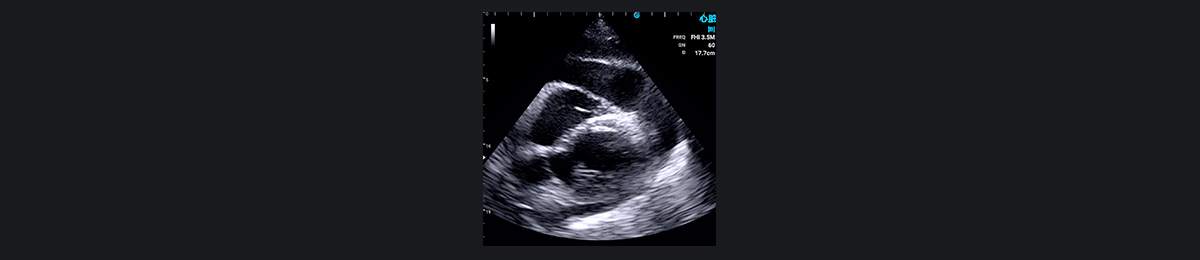

Ò»ÃûÖÐÄêÄÐÐÔ»¼ÕßÒò×ó²àÐØÍ´ÈëÔº¡£¿ìËÙÊÖ³Ö³¬ÉùɨÃ裨ÐļâËÄÇ»ÊÓͼºÍ¶ÌÖáÊÓͼ£©ÏÔʾÐļâºÍǰ±ÚµÄÔ˶¯ÏÔ׿õÉÙ£¬Ìáʾ ACS¡£Ë«Áª¿¹ÑªÐ¡°åÖÎÁÆËæºó½øÐÐ PCI ֤ʵ×óǰ½µÖ§¶¯Âö±ÕÈû¡£

³ÉÈËÐØÍ´Í¨³£ÊÇÓɹÚ×´¶¯Âö¼²²¡ÒýÆðµÄ£¬µ«È·¶¨È·ÇÐÔÒòÐèÒª½øÒ»²½µ÷²é¡£Í¨¹ý³¬Éù²¨³ÉÏñ£¬SonoEye ÊÖ³Öʽ³¬Éù²¨¿ÉÒÔÇø·ÖÐØÍ´ÊÇ·ñÊÇÐÄÔ´ÐԵġ£ËüÔÚÕï¶ÏÐÄѪ¹ÜÒì³£·½ÃæÌرðÓÐЧ£¬ÀýÈç·ÊºñÐÔ¹£×èÐÔÐ¡¡¢Ö÷¶¯Âö°êÏÁÕ¡¢Ö÷¶¯Âö¼Ð²ã¡¢ÐİüÑס¢¶þ¼â°êÏÁպͷÎ˨Èû¡£

·ÊºñÐÔ¹£×èÐÔÐ¡